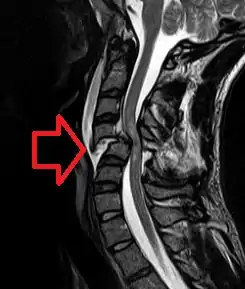

![]() | |

| MRI از مهرههای شکسته شده و جابجا شدهای که طناب نخاعی را می فشرند. | |